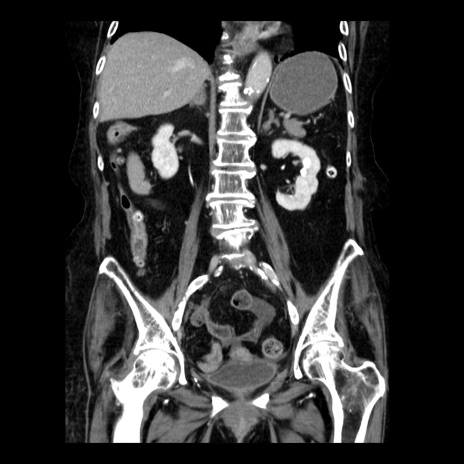

症例14(冠状断像)

【症例】 90歳代女性

【主訴】 腹痛・嘔吐

【現病歴】今朝から左側腹部痛を認めた。 経過観察していたが、嘔吐を認めたため来院。

【既往歴】 子宮癌術後

【身体所見】 意識清明、BP 127/54mmHg、P 98bpm Sp02 95%(RA)、BT 35.8°C、腹部平坦・軟腸ぜん動音聴取良好、右下腹部圧痛(+) 反跳痛なし

【データ】WBC 9800、CRP 0.46